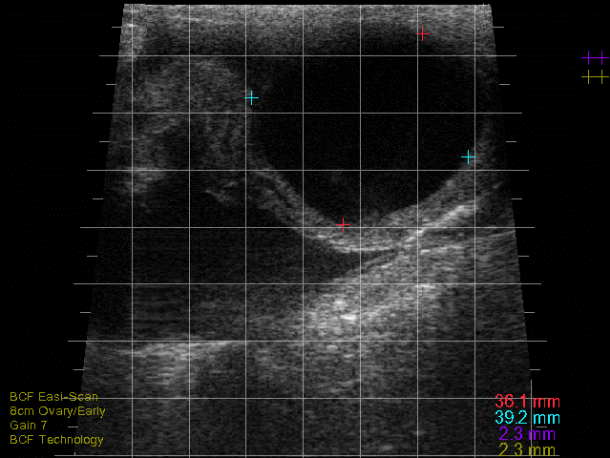

Follicular cysts are typically large, thin-walled (<2-3mm), round, black structures that are often single but can be multiple (see Photo 1)2,4. Traditionally, follicular cysts were defined by being greater than 25mm in diameter and persisting for longer than 10 days but recent work would indicate that follicular cysts can be present and only measure 16-17mm in diameter2. Cows with follicular cysts will have low peripheral progesterone concentrations and typically present anoestrous but can be nymphomaniacal if the cyst is actively secreting oestradiol4. However, that stated, follicular cysts are still dynamic structures which can luteinise (forming a luteal cyst), or become inactive and regress. In situations where they have begun to regress, the cystic structures can be noted in cows who have started to cycle again (i.e., some of these cows will have CLs) or even those cows who have become pregnant.